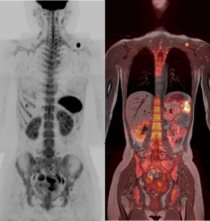

DWIBS

当院では、全身のがんを低侵襲で検出できる新しい画像検査技術「DWIBS(拡散強調全身MRI)」を開始しました。

DWIBSは、MRIを用いて全身を撮影することで、PET-CTのようにがんの早期発見を可能にする検査です。放射線被ばくがなく、造影剤も使用しないため、体への負担が少ないのが特長です。特に以下のような方におすすめです。